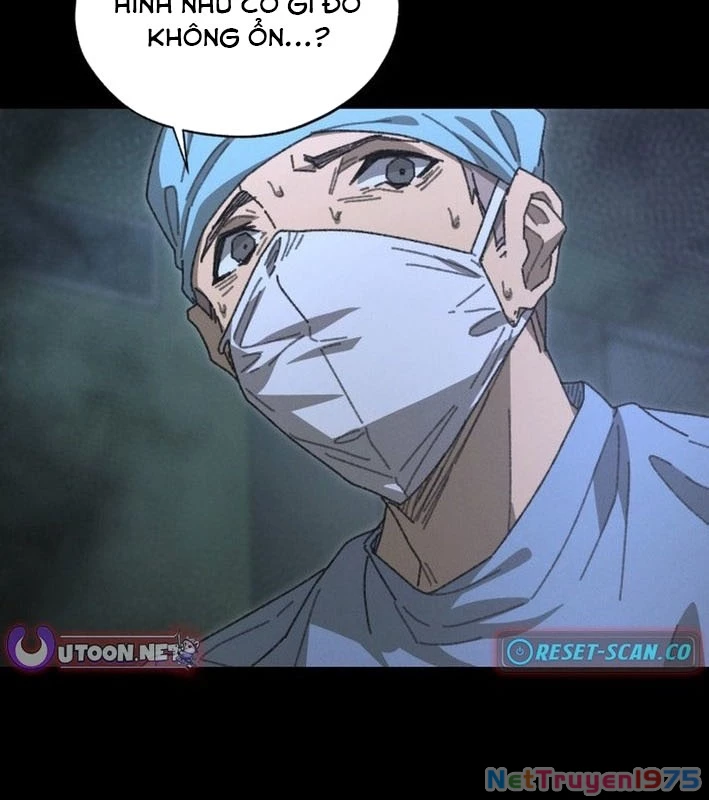

Kẻ Chôn Cất Quái Vật - Chapter 1